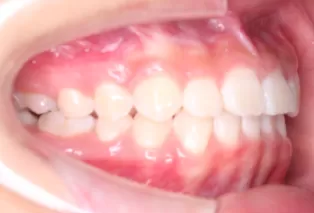

Photos intra-orales